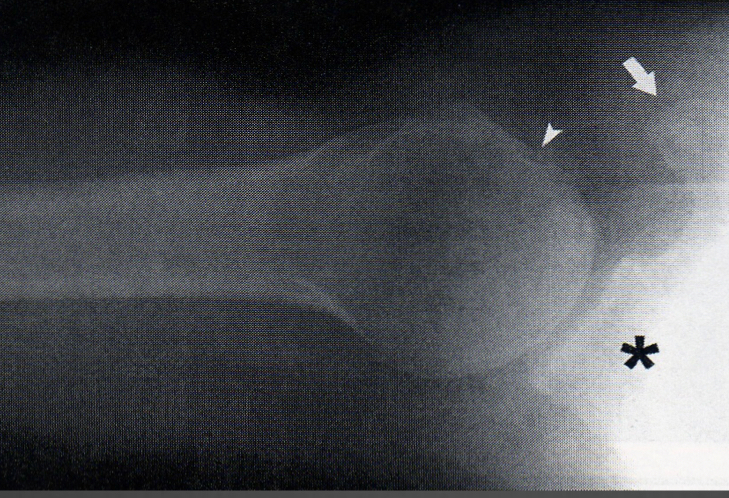

Small fracture of glenoid rim that is frequently caused by reductions that don’t get enough clearing or dislocation

Bankart Fx

bankhart